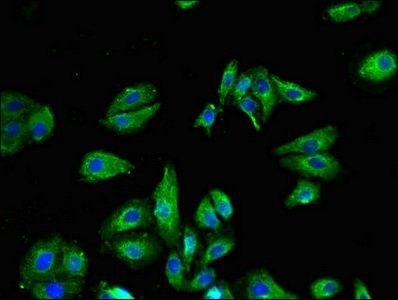

Immunofluorescence analysis of HepG2 cells using TRPV1 antibody